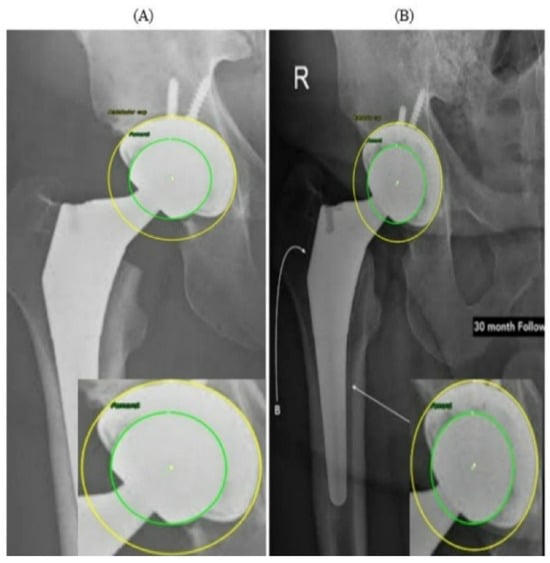

Figure 11 presents two radiographs from the same patient acquired at different time points. In the PRE image (Figure 11A), the prosthetic components appear well aligned, with symmetric and uniform joint spaces surrounding the femoral head. No displacement or asymmetry is observed, and the head is centrally positioned within the AC. In contrast, the 30-month POST radiograph (Figure 11B) shows a subtle superior migration of the femoral head. This displacement produces a clear difference in the superior joint space, together with a relative widening of the inferior gap, indicating superior polyethylene wear. A mild medial shift of the femoral head center is also visible, reflected by narrowing of the joint space on the medial side and confirming the occurrence of medial wear. Thus, the joint space that was initially symmetrical has become asymmetrical over time due to combined superior and medial displacement. This pair of radiographs clearly illustrates the progression of wear over the 30-month period, demonstrating a consistent superomedial direction of femoral head penetration within the AC. Both radiographs in Figure 11 originate from the external evaluation dataset and were not included in the training process.

Figure 11.

Example 1 of PRE–POST radiographs with detected femoral head and AC circles. (A) PRE radiograph demonstrating a centered femoral head within the acetabular cup. (B) POST radiograph showing superior displacement of the femoral head consistent with wear progression.

In Figure 12, the PRE radiograph (A) shows the femoral head well-centered within the AC, with a uniform joint space superiorly and medially. The alignment between the two circle centers indicates that no measurable migration has yet occurred. In the POST radiograph obtained several years later (B), the femoral head is positioned closer to the superior aspect of the cup, indicating a clear difference in the superior joint space. This pattern is consistent with progressive superior polyethylene wear. Additionally, a slight medial shift of the femoral head center is visible, demonstrating progressive medial wear over time. Overall, the comparison between (A) and (B) shows a combined superior and medial wear. Similar to Figure 11, the radiographs in Figure 12 were obtained from the external, unseen dataset and were never used for training or validation.

Figure 12.

Example 2 of PRE–POST radiographs with detected femoral head and AC circles. (A) PRE radiograph demonstrating a centered femoral head within the acetabular cup. (B) POST radiograph showing superior displacement of the femoral head consistent with wear progression.

These findings reinforce the value of combining visual and quantitative evidence when interpreting longitudinal THA radiographs. While subtle migration patterns can be difficult to identify through visual inspection alone, particularly when the displacements are only a few pixels, the automated circle-based analysis provides a reproducible framework for detecting even minimal deviations from baseline alignment. The PRE–POST differences captured in Figure 11 and Figure 12 demonstrate how small variations in center position and joint-space geometry accumulate over time to form clinically meaningful wear trajectories. Importantly, the refined circle estimates reduce the influence of image noise, projection variability, and partial rim visibility, ensuring that the observed displacements reflect true anatomical change rather than measurement artifacts. By integrating both geometric overlays and numerical wear metrics, the system enables a clear linkage between qualitative radiographic appearance and quantitative displacement values. This dual-layer interpretation helps distinguish early progressive wear from normal postoperative variation and supports more consistent longitudinal monitoring of implant performance.

Two representative wear cases were quantitatively summarized in Table 3 and Table 4, each including a pair of PRE and POST radiographs along with the automatically computed medial, superior, and resultant wear components. In both examples, the system successfully produced consistent numerical outputs after scale normalization. These examples demonstrate the ability of the proposed framework to extract reliable and fully automated wear measurements. When a magnification factor is available, pixel-based wear values can be converted to millimeters using the following:

where is the pixel-to-millimeter magnification factor. The PRE radiograph is taken as the reference; if the POST image has a different magnification, it is first rescaled to the PRE scale before computing medial, superior, and resultant wear.

Table 3.

Automatic measurements and calculated wear values for Figure 11.

Table 4.

Automatic measurements and calculated wear values for Figure 12.